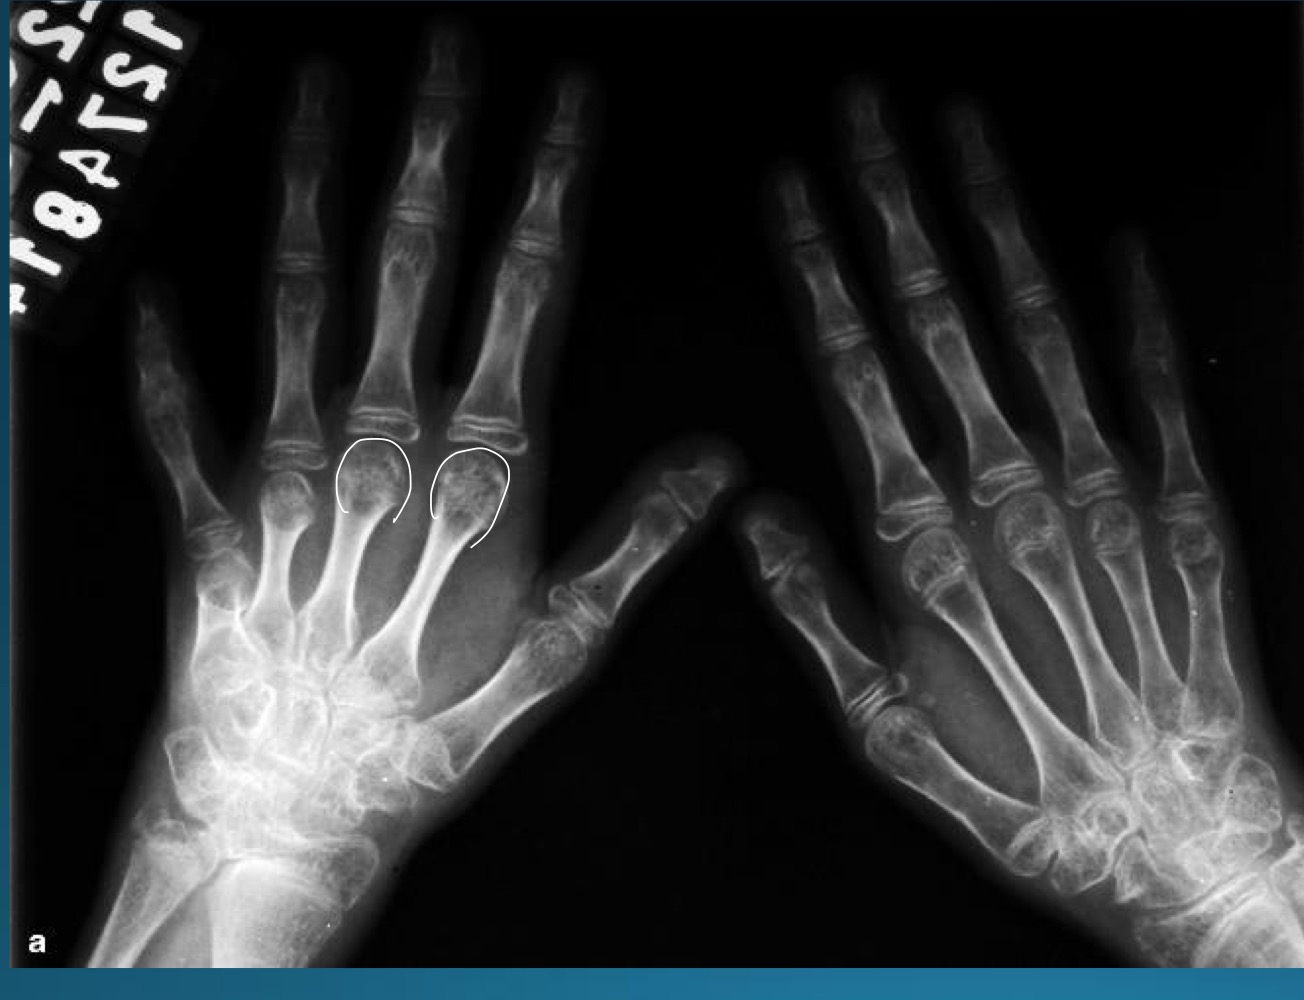

what are the findings in this image?

erosive osteoarthritis

waht are the features denoting erosive osteoarthritis on radiograph?

central erosions creating gull wing sign

EOA likes what joints?

DIP, PIP, 1st CMC